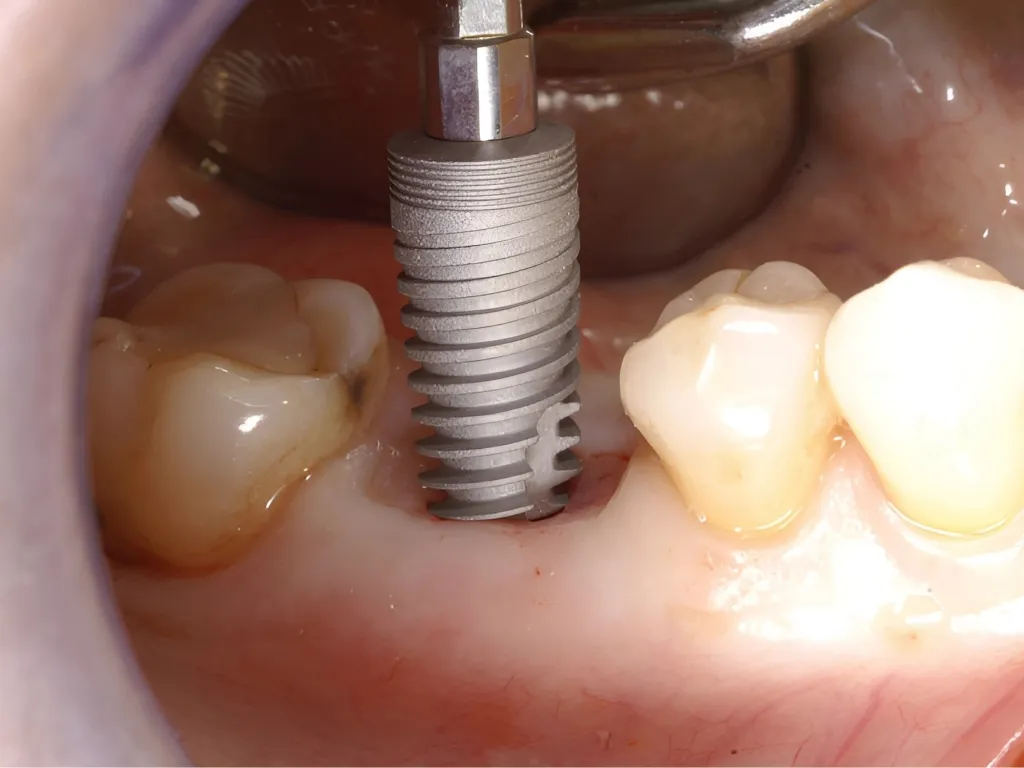

Assessment of Crestal Bone Loss and Degree of Success

İmplantasyon ve protetik yükleme sonrası osseointegrasyon başarısı ve ilk yıl sonunda oluşan krestal kemik kayıpları